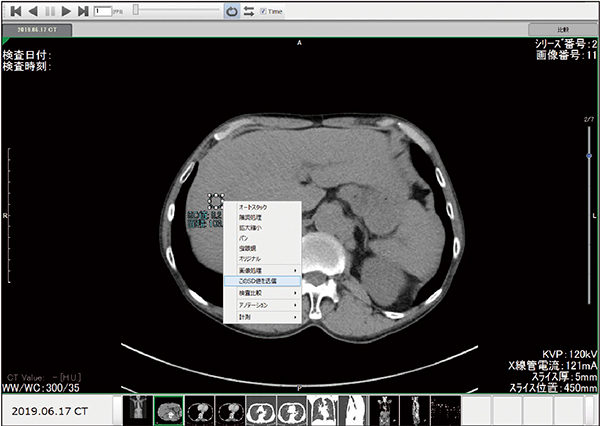

(4) 中央値のSD値をシステム上で計測し,値を送信して当院規定のSD値*と比較する(図4)。

図4 SD計測・送信画面